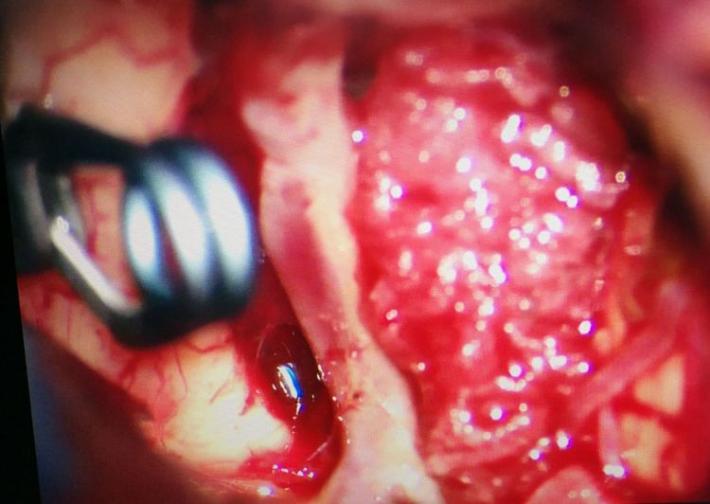

右侧翼点入路,解剖脑池系统,见前交通动脉瘤向右前伸入右侧视神经下方。予以夹闭。

探查右脉前小动脉瘤,未破,予以包裹。手术完毕。